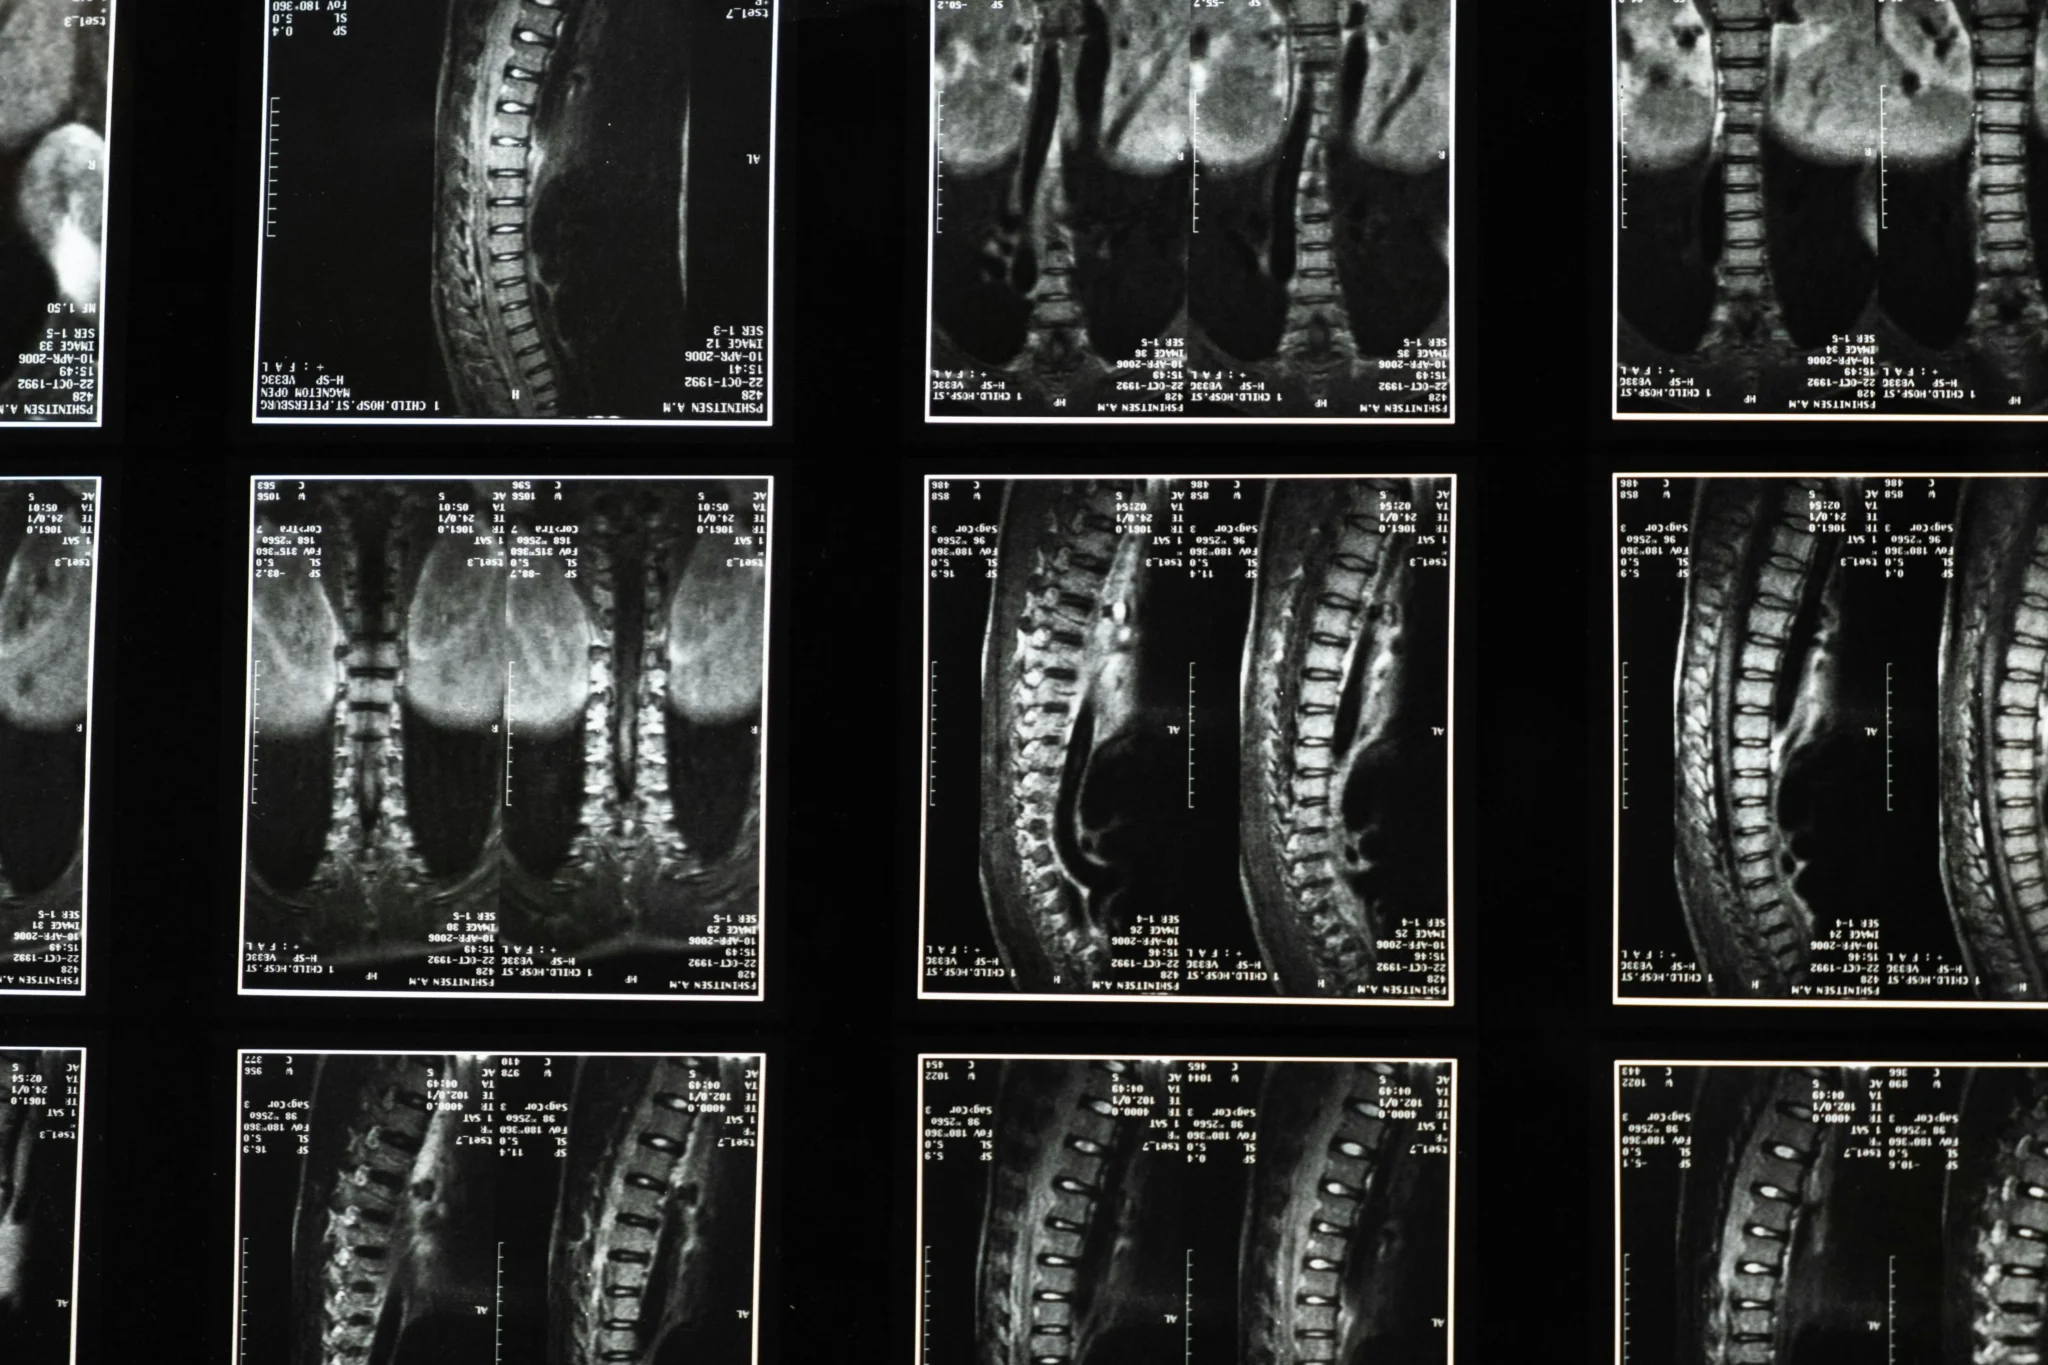

A cirurgia de coluna é um procedimento médico realizado para tratar doenças e lesões da coluna vertebral, como hérnias de disco, estenose espinhal e escoliose. Envolve técnicas avançadas para descompressão, estabilização ou correção estrutural. Visa aliviar a dor, melhorar a mobilidade e restaurar a função neurológica.

A subespecialidade da neurocirurgia que trata condições da coluna vertebral, como deformidades e tumores, oferece desde cirurgias complexas até técnicas minimamente invasivas. Estas últimas utilizam pequenas incisões, proporcionando menos dor, recuperação mais rápida e, em alguns casos, alta no mesmo dia.

As hérnias de disco na coluna são condições que ocorrem quando o núcleo pulposo do disco se desloca para fora do espaço intervertebral, podendo comprimir as raízes nervosas ou a medula espinhal, dependendo da região da coluna acometida.

A artrodese da coluna é um procedimento cirúrgico realizado para aliviar a dor e melhorar a estabilidade da coluna em algumas doenças, como hérnia de disco, espondilolistese (“escorregamento” de vértebras), canal lombar estreito, mielopatia cervical espondilótica, escoliose, tumores metastáticos dentre outras patologias.